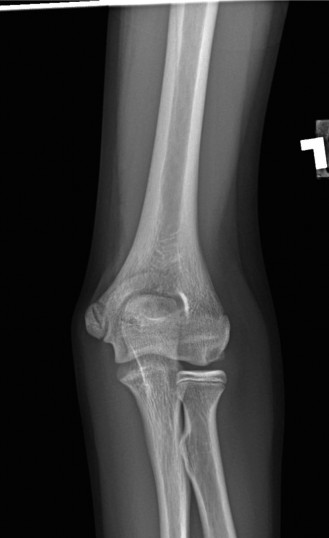

A 45-year-old carpenter presents with shoulder pain that has been ongoing for the last 3 months. He denies any significant injury. He describes night pain and significant discomfort at work. His imaging is shown in Figure 2–9. What is the most likely diagnosis?

Figure 2–9_From Shi LL, Mullen MG, Freehill MT, et al. Accuracy of Long Head of the Biceps Subluxation as a Predictor for Subscapularis Tears. _Arthroscopy 2015;32(4):615–619.

Discussion

The correct answer is (A). Medial subluxation of the biceps tendon as seen in this MRI is commonly associated with a tear of the subscapularis tendon which attaches to the lesser tuberosity. This patient’s pain may in part be attributable to the subscapular tear and this should be evaluated for during physical examination. Supraspinatus tears (Answer B) cannot be easily visualized on axial views and are not associated with medial biceps subluxations. A labral tear and ALPSA lesion (Answers C and D) are not seen on the images provided. The question stem and MRI are not suggestive of shoulder instability (Answer E). Objectives: Did you learn...? Diagnose and treat acute rotator cuff tears?